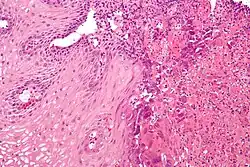

Esofagite Eosinofilica

É uma doença inflamatória com características alérgicas, causada por um denso infiltrado de eosinófilos no epitélio esofágico. O diagnóstico é feito por endoscopia digestiva alta, com identificação de lesões sugestivas e realização de biópsias. A análise destas amostras deve demonstrar a presença de pelo menos 15 eosinófilos por campo de grande aumento. O tratamento baseia-se em dietas específicas bem como medicamentos como corticóides.[1]